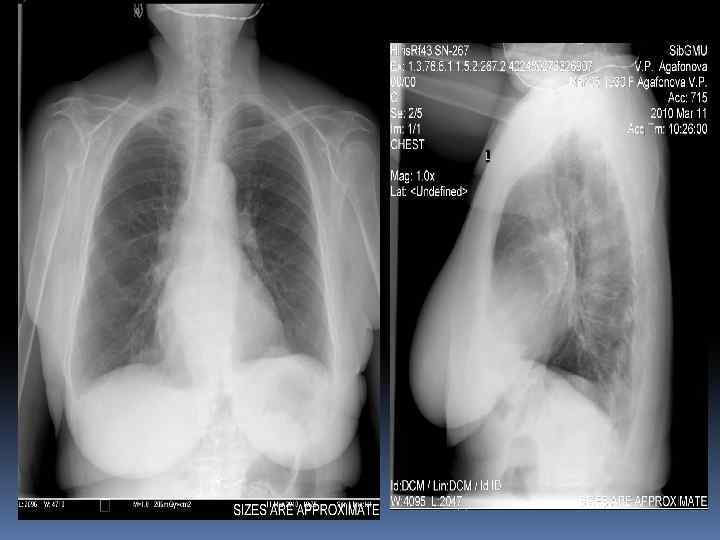

Изменение гемодинамики малого круга – ЛВГ, ЛАГ, интерстициальный отек

Изменение гемодинамики малого круга – ЛВГ